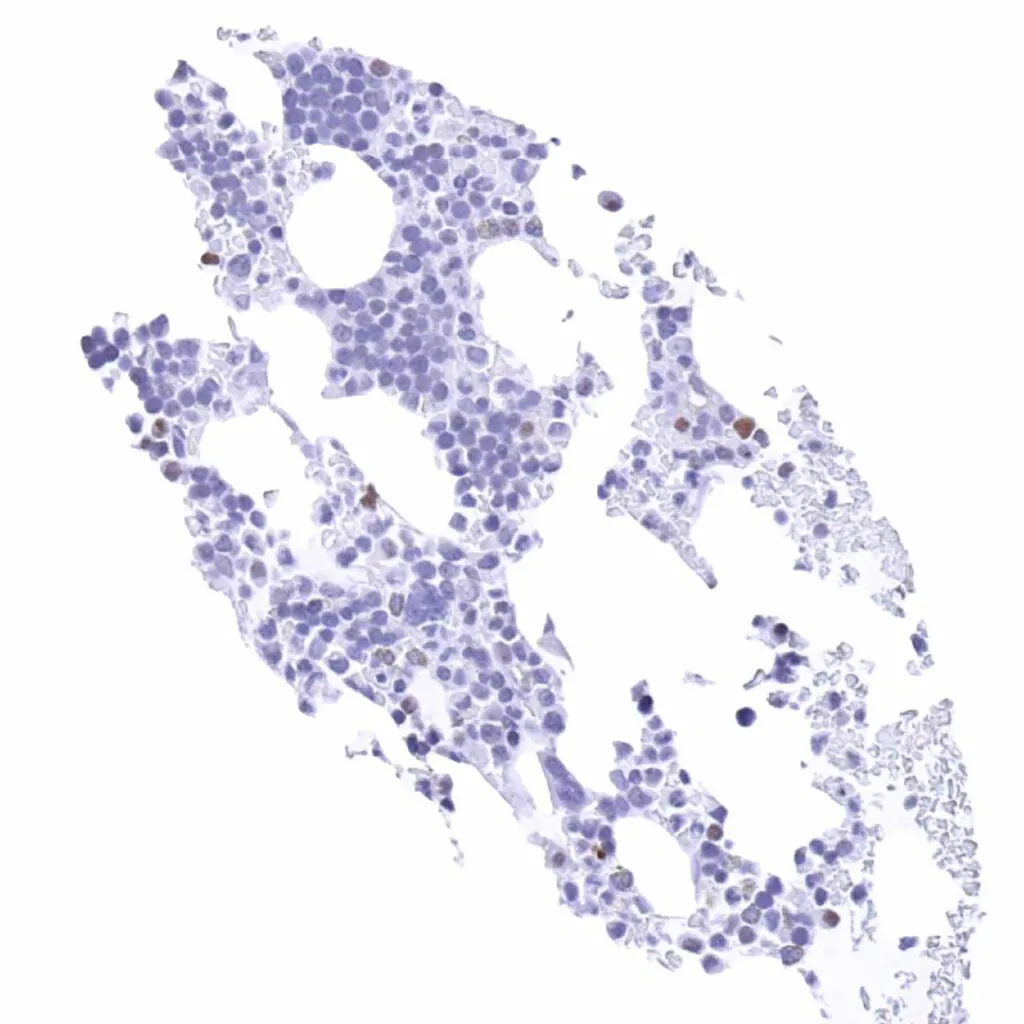

Spleen – Weak Cyclin E1 staining of only a small fraction of cells